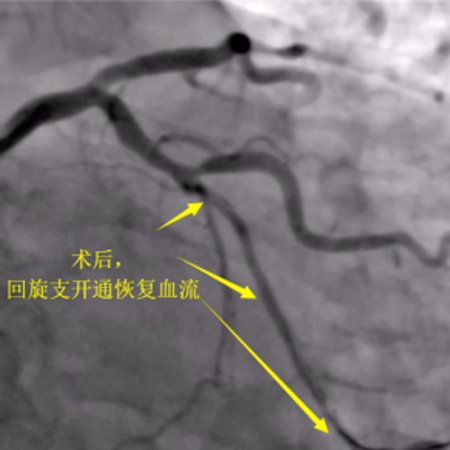

12月3日,老吴第三次进入导管室,这次老吴很轻松,和我还有说有笑,而我却承受了比上次更大的压力,因为老吴是带着肯定而来,带着信任而来。结果左侧造影回旋支远端的同侧逆向供应血流消失了,不得不穿刺左手进行右冠造影为左冠回旋支导丝前进提供方向,皇天不负有心人,经过重重困难最终再次顺利开通了闭塞的回旋支,这一刻如释重负,汗水打湿了衣物,浸透了铅衣!

造影可见:前降支中段发出对角支后极重度狭窄,可见侧支循环右冠中远端,回旋支发出钝缘支后闭塞,可见钝缘支侧支循环回旋支远端;右冠中段闭塞。